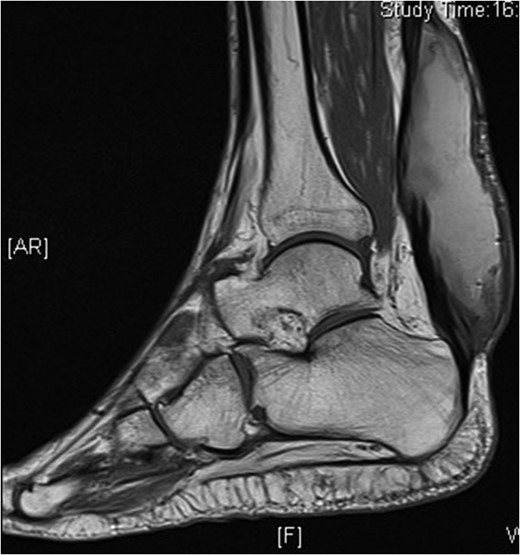

An MRI scan showed a 10 × 3.6 × 3 cm collection within the Achilles tendon that was thought to be an evolving haematoma, along with debris in the periphery. Continuity of the Achilles was demonstrated (Fig. 2).

MRI scan. T2 PD fat sat sequence sagittal image of right ankle showing high-signal collection within the Achilles tendon.